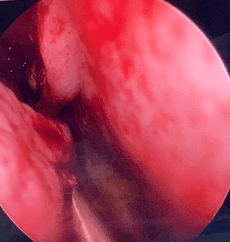

COBLATION Assisted Surgeries

A minimally invasive, low thermal technology for effective dissection and removal of tissue, COBLATION Technology has been used for ENT procedures such as tonsillectomy, turbinate reduction, laryngeal lesion debulking and soft palate.

While conventional electrosurgical devices use high temperatures to remove and cut tissue, our COBLATION Technology creates a controlled, stable plasma field to precisely remove tissue at a low relative temperature, resulting in minimal thermal damage to surrounding soft tissues. Its features include very limited depth of thermal penetration; minimal collateral tissue damage; localised effect; and controlled, volumetric tissue removal. Coblation is often preferred for its ability to reduce surgery duration and pain, minimise bleeding, and speed up recovery times in patients undergoing certain types of surgery.